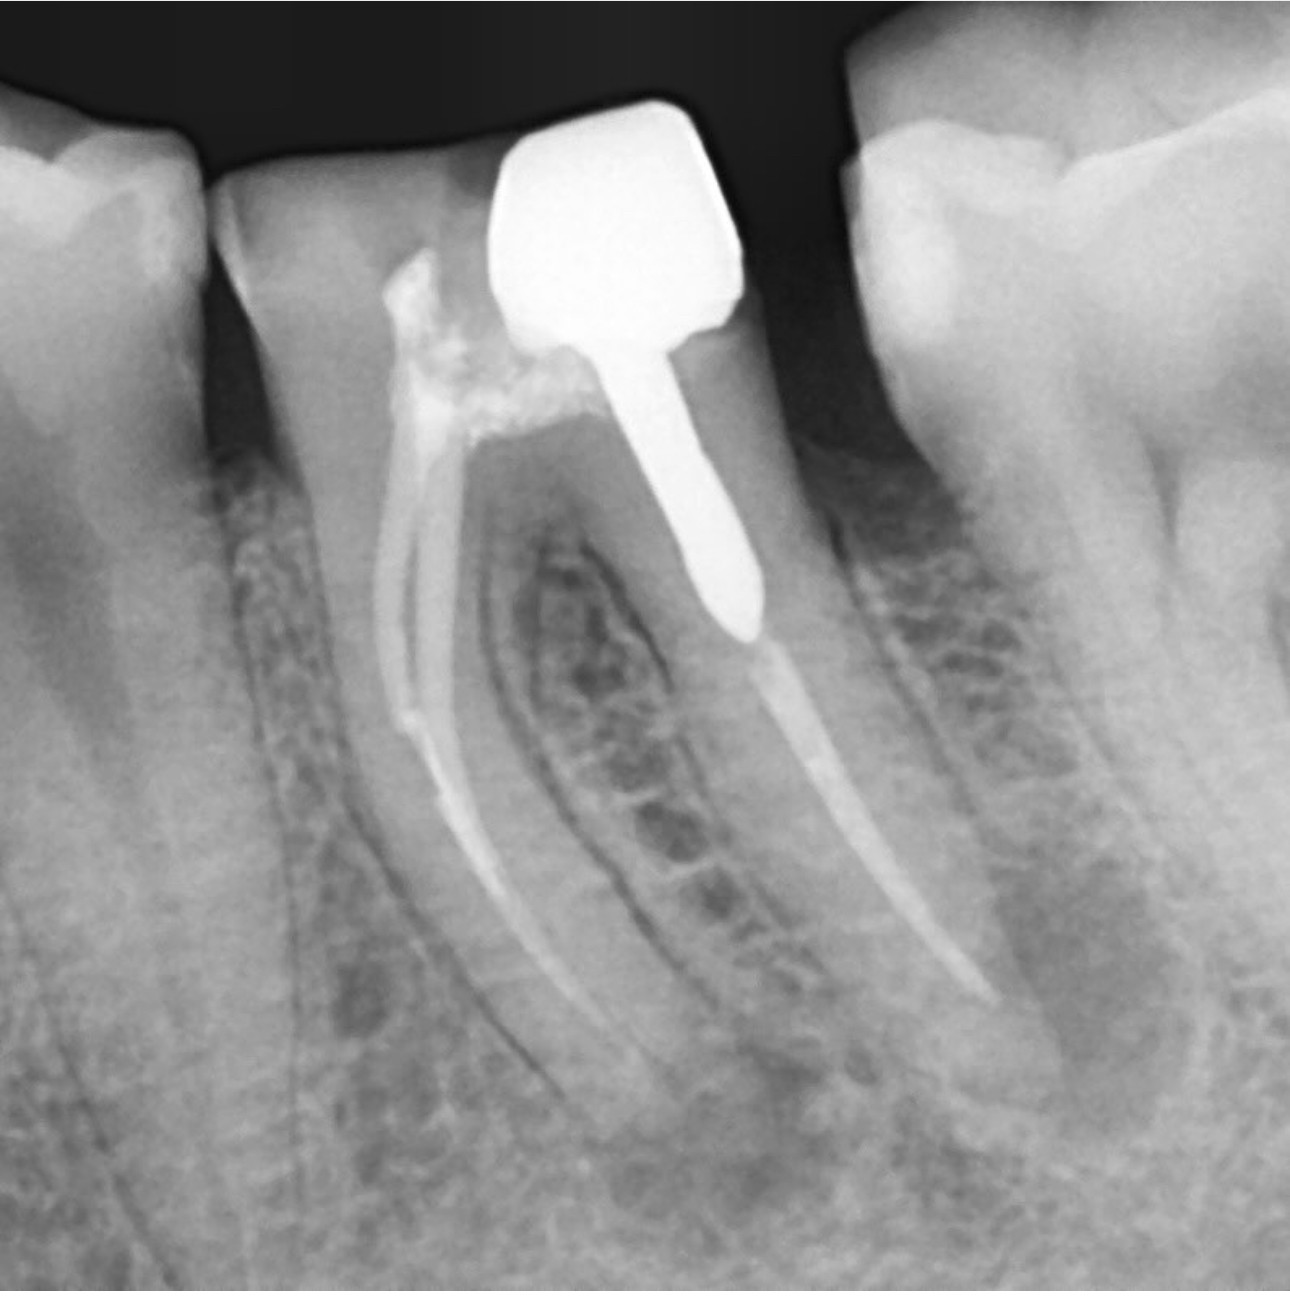

1.  What option can describe the post placement in the X ray bellow for the tooth # 2.5?